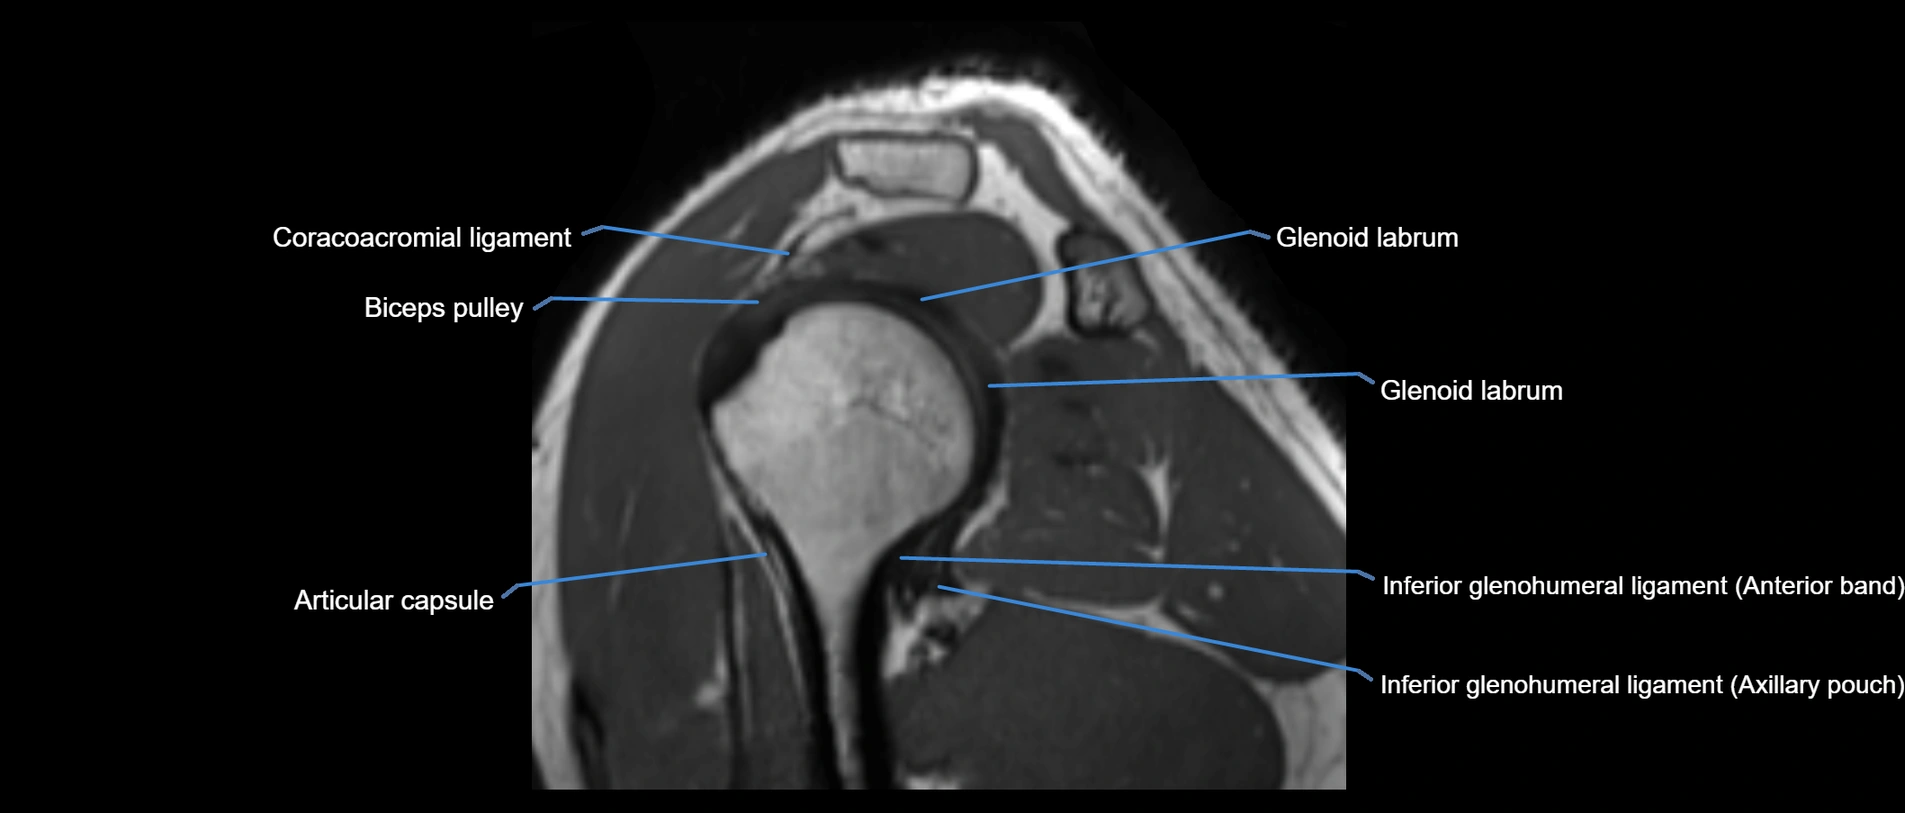

MRI images

image

MRI Appearance

• T1-weighted images:

• Normal ligament: Low signal (dark linear band) spanning acromion to clavicle.

• Surrounding fat planes: Bright, delineating the ligament clearly.

• Marrow of clavicle and acromion: Bright due to fatty content.

• Tears: Discontinuity or irregular thickening with intermediate-to-bright signal.

• Chronic injury: Thinning, fraying, or irregular low-signal fibers with adjacent scarring.

• T2-weighted images:

• Normal ligament: Low signal, homogeneous.

• Partial tear or sprain: Focal hyperintensity or thickening.

• Complete tear: Discontinuity with fluid-bright gap between clavicle and acromion.

• Associated edema: Bright signal in distal clavicle or acromion marrow.